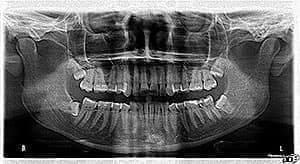

К стоимости самой операции стоит добавить цену диагностики: осмотра у стоматолога, рентгенографических снимков патологического и рядом стоящих зубов. Также может понадобиться ортопантомограмма для подтверждения или опровержения стоматологом диагноза нарушения прикуса.

Удаление зуба мудрости – хирургическое вмешательство, направленное на ликвидацию коронки и корня «восьмерки». Такие единицы также называют «третьи моляры». У людей может выйти один или два, а также все четыре зуба мудрости, причем в возрасте после восемнадцати лет или даже после 50-ти. В большинстве случаев их прорастание приносит пациентам массу дискомфорта – от банальной боли из-за неправильного положения до серьезных проблем с прикусом.